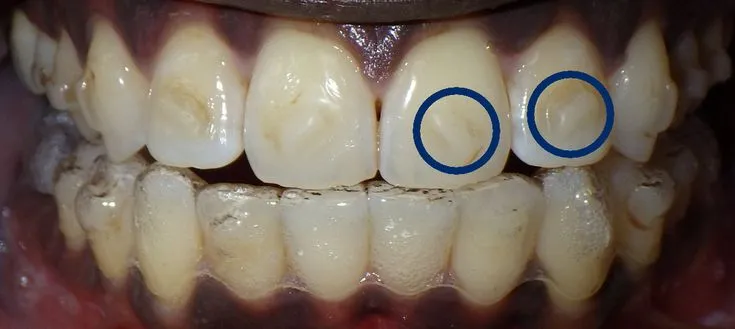

Invisalign attachments are small, tooth-colored shapes that are bonded to your teeth. These attachments serve as anchors, providing Invisalign aligners with something to grip, enabling the aligners to apply the necessary force to move teeth into their desired positions. They can be made of composite resin and are designed to blend seamlessly with your teeth. The number and placement of attachments vary depending on the complexity of your treatment plan. Understanding their purpose is crucial, as they can affect how whitening products interact with your enamel. Attachments help with a variety of tooth movements, including rotation, intrusion, and extrusion, which are critical for achieving a properly aligned smile. Without attachments, the effectiveness of Invisalign treatment could be significantly reduced.

Attachments can present challenges when it comes to teeth whitening. They act as barriers, preventing the whitening agents from reaching the entire surface of the tooth evenly. This can lead to uneven whitening, where the areas covered by attachments appear less bright than the exposed tooth surfaces. Because the attachments are bonded to the teeth, the whitening process can be slightly more complex than when using traditional methods. It’s important to consider the timing and method of whitening in relation to the presence of attachments. Proper planning with your dentist or orthodontist is vital to ensure the best possible outcomes, minimizing the risk of any aesthetic compromises to your smile during and after your Invisalign treatment.

Uneven whitening can occur when the areas of your teeth covered by attachments appear less bright. Discuss this issue with your dentist or orthodontist. In some cases, your dentist may be able to apply more whitening gel around the attachments to improve the results. If the discrepancy is significant, your dentist may remove the attachments, whiten your teeth, and then reattach the attachments. Another option is to use a different whitening method that may provide more uniform coverage. Proper technique and planning are important to avoid uneven whitening, and adjustments may be needed throughout the process to achieve a consistent outcome.